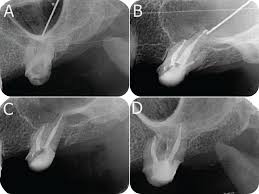

Pdf Effects Of Surgery And Topical Medication On Eosinophilic Granulomatosis With Polyangiitis With Otitis Media And Sinusitis A Case Report

Pdf Effects Of Surgery And Topical Medication On Eosinophilic Granulomatosis With Polyangiitis With Otitis Media And Sinusitis A Case Report from www.researchgate.net

However, it's possible — and even somewhat more likely — to have chronic sinusitis. (b, c) polyps in the middle nasal meatus on the left side and in the olfactory cleft on the right side can be seen. Or is it exacerbated by the use of my cpap at night? Medication to treat nasal polyps and chronic sinusitis. But most were dislodged after 14 weeks. Your healthcare provider will take a health history and do a physical exam. No one knows exactly why some people get nasal polyps. Small nasal polyps may not cause symptoms. To remove any nasal polyps, your ent physician uses a small nasal telescope, and lances the polyp. Surgery, such as functional endoscopic sinus surgery (fess), may be. Nasal polyps are noncancerous growths caused by long term swelling inside of your nose. Mometasone nasal spray 200 mcg once or twice daily is appropriate to reduce symptoms and it may decrease the size of nasal polyps in patients who have chronic rhinosinusitis. They result from chronic inflammation due to asthma, recurring infection, allergies, drug sensitivity, or.